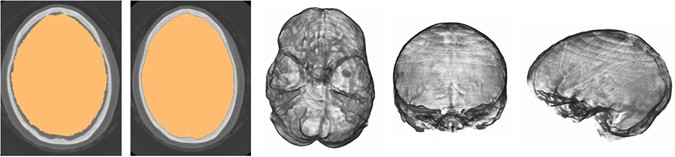

The result of intracranial segmentation after atlas registration (first panel) and refined segmentation after levelset evolution (second panel). Corresponding volume renderings (axial view from the skull base, coronal and sagittal view).